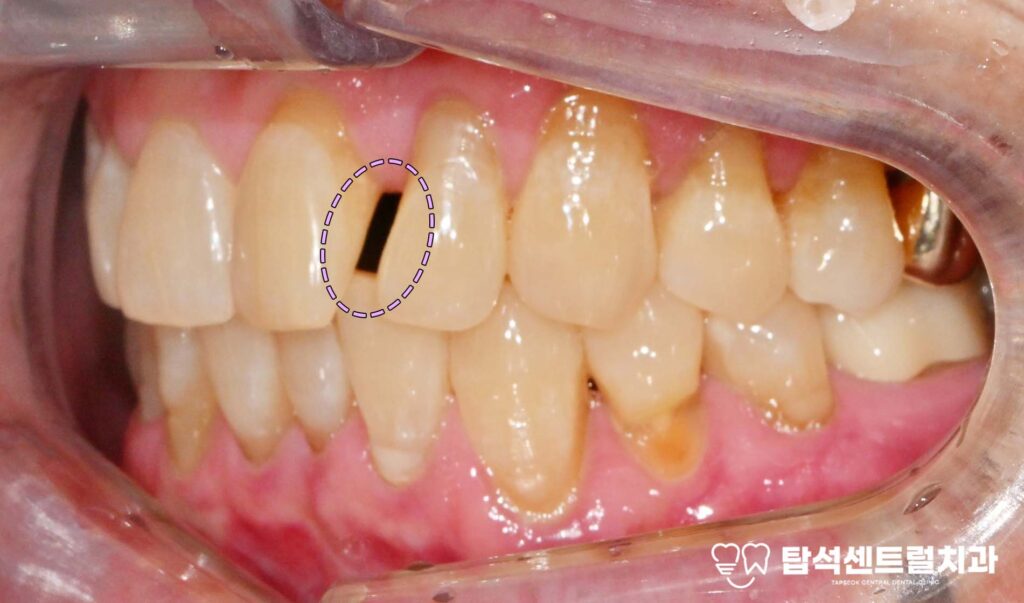

벌어진 앞니 사이 공간, 어떻게 개선할 수 있을까

벌어진 앞니 사이에 공간이 있으면

작은 공간이나 치아 형태 변화가

적게 필요한 경우에는

레진 치료를 고려할 수 있습니다.

더 넓은 범위의 개선이 필요하면

라미네이트나 크라운 같은

보철을 선택하기도 합니다.

벌어진 앞니 레진 치료의 특징

레진은 실제 색상과 유사한

재료를 사용하여 표면에

직접 부착하는 방식을 말합니다.